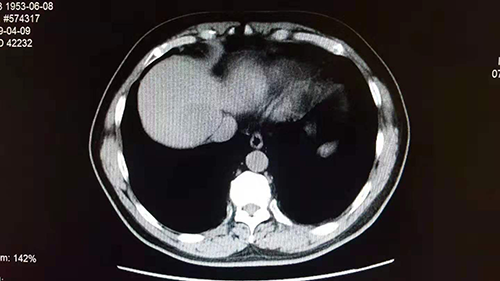

美超体检中心客户、男性、65岁,有“小三阳”多年。2019年5月体检,超声和CT影像学均显示肝血管瘤,并与去年比较结果相同,肿瘤指标甲胎蛋白检查显示阴性。超声与CT图像在比较分析时发现,超声与CT初步判读的肝血管瘤并不在肝脏的同一部位(同一病灶),经对病灶进行定点超声扫查,确认为肝实质性占位,随后在东方肝胆医院获得手术切除。